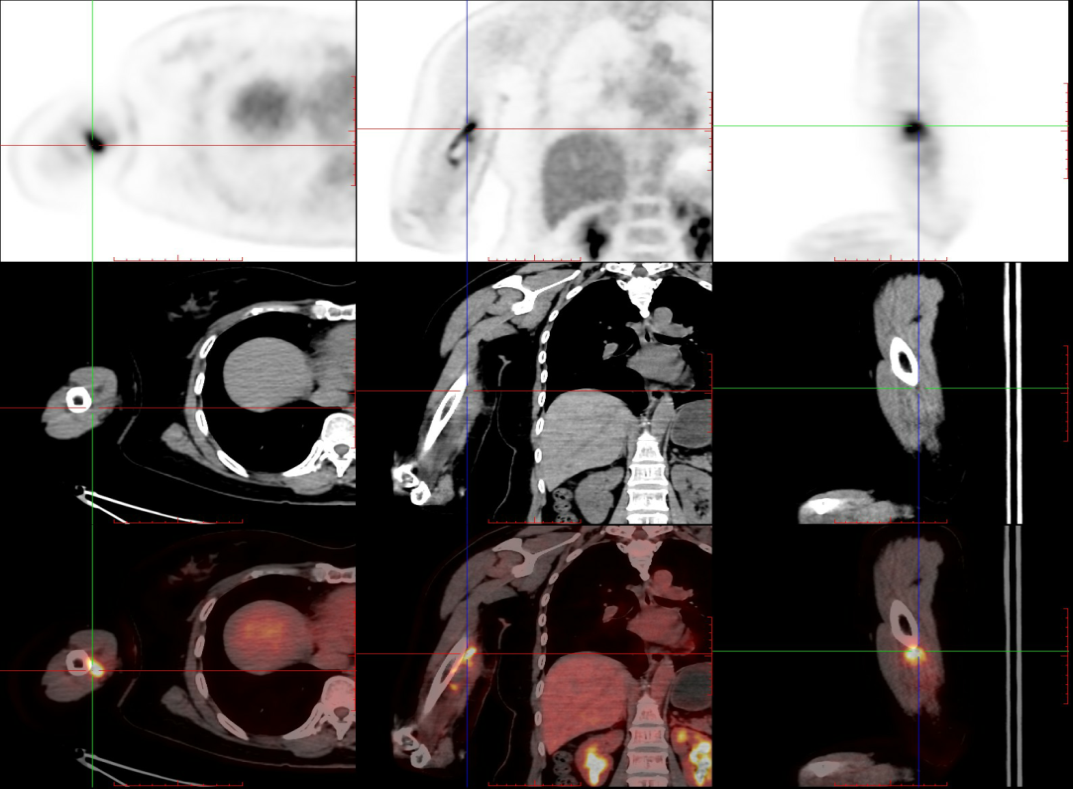

上图示右上臂内侧术后改变,术区可见FDG药物摄取不均匀增高,提示手术未切除干净,肿瘤有残留。

上图示右上臂内侧术后改变,术区可见FDG药物摄取不均匀增高,提示手术未切除干净,肿瘤有残留。 上图示右侧腋窝及右侧锁骨上区可见不等大小的淋巴结,FDG药物摄取增高,提示淋巴结转移。